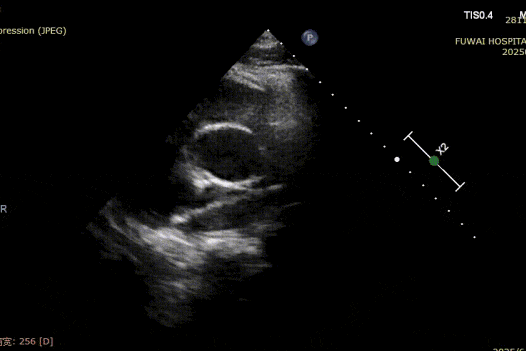

At Fuwai Hospital Shenzhen, Dr. Lu Yaoxing's team recently performed a successful transcatheter closure of a secundum atrial septal defect (ASD) using a MemoSorb biodegradable occluder in a 34-year-old male patient with a rare coronary anomaly.

1. The ASD was central in location, with a measured diameter of approximately 8.1 mm (bicaval view) and 8.2 mm (aortic short-axis view).

2. Coronary CTA revealed an anomalous origin of the left circumflex artery (LCX) from the right coronary sinus, with a course between the aorta and left atrium.

3. The distance between the ASD and the aberrant LCX was only about 6 mm.

4. There was no aortic rim, and the inferior and posterior rims were relatively soft.